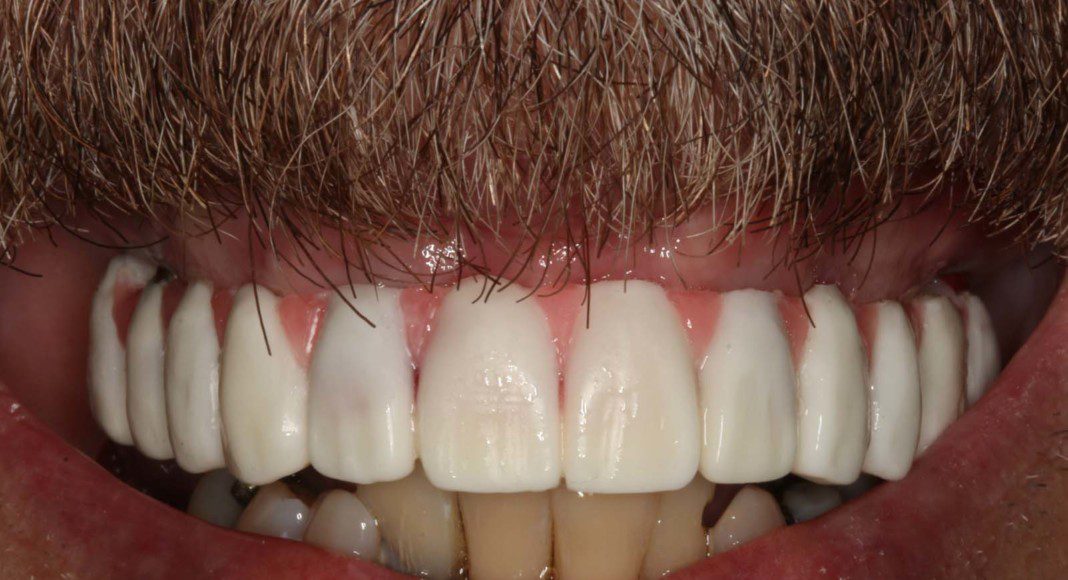

Mirror view of the tissues before delivery of the zirconia, implant bridge. Note the excellent volume of good, pink tissue (keratinized tissue). This good tissue is what allow the bone to remain healthy and full for many years if not forever.

Right lateral (mirror) view of bridge. Note the “normal” contours that mimic natural teeth. Slight metal exposure of implant #4. Nothing can be “perfect” and we try to keep this from happening. However, some patients have existing bone loss that prevents perfection.

Mirror view of final implant bridge. The screw holes have been sealed with composite resin. This plastic filling material can be easily removed to remove and clean or service the bridge. We call this “retrievability”.